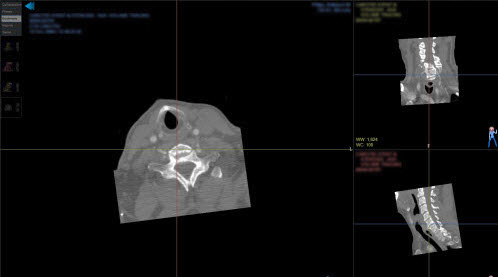

Sample layouts and views

The following examples show common ways to arrange images using study layouts and views. Available views depend on your NilRead implementation.

Multiple monitors

Each monitor can have its own study layout. In the following example, the first monitor displays two coronal MPR views and the second monitor displays an axial MPR.